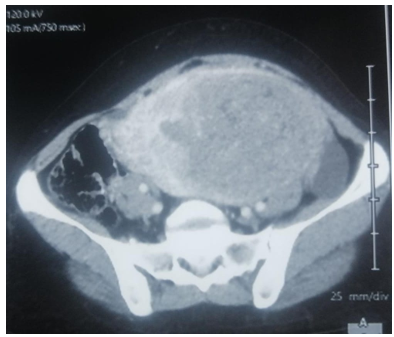

Abdomino-pelvic CT objectified the presence of an intra-uterine tissue mass lateralized on the left heterogeneously enhanced after injection of PDC, fairly well limited, seat of the area of necrosis, measuring 127x80x165cm. Associated with left external iliac adenopathy of 8 mm Probably related to uterine myoma.

Fig 3: CT appearance of a tissue mass of hetero-dense uterine origin poorly limited in places measuring 15 cm